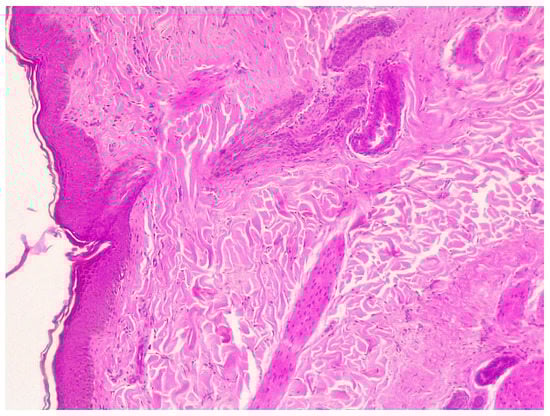

2.4.4. Histopathology